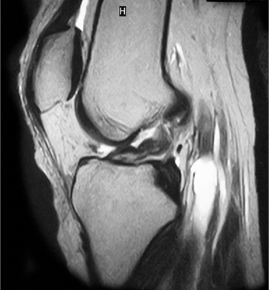

• ACL 손상 방사선 사진1